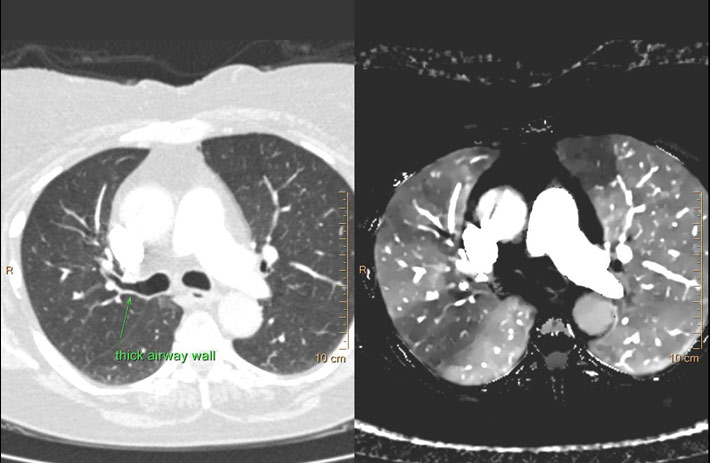

Mit dem Spektral-Detektor-CT werden Spektraldaten automatisch bei jedem Scan erfasst. Die Informationen stehen jederzeit auf der Scankonsole, der CT-Workstation sowie an jedem PACS-Arbeitsplatz zur Verfügung, sodass es nicht notwendig ist, den Patienten erneut zu scannen, bspw. wenn initial zufällige Anomalien festgestellt wurden. Dadurch profitieren Anwender durch eine höhere Diagnosesicherheit und weniger Nachuntersuchungen auf anderen bildgebenden Systemen. Unsere Fallsammlung zeigt, welchen klinischen Mehrwert der Spektral-Detektor-CT in unterschiedlichsten Anwendungsbereichen in der klinischen Routine bringt. Jede Woche gehen neue Fälle live.